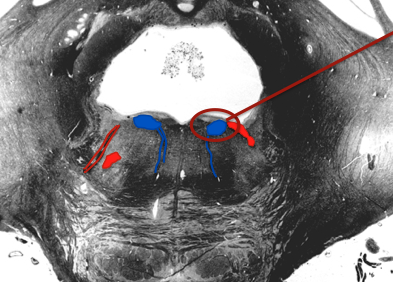

Approximately half of the second order neurons of cochlear nuclei

send axons across the midline, through the region containing the ____

medial lemniscus

what is the trapezoidal body?

contains crossing auditory axons and the medial lemniscus

auditory axons from the cochlear nuclei, no matter if they cross or not, synapse in the

supeiror olive and other auditory nuclei